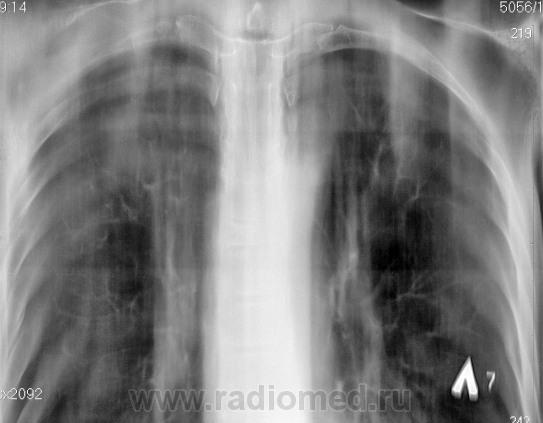

Справа на верхушке инфильтративная тень. Слева в задних отделах мелкие буллы.

На последнем срезе тень в 1 сегменте, мелкие полости в верхних долях с обеих сторон.